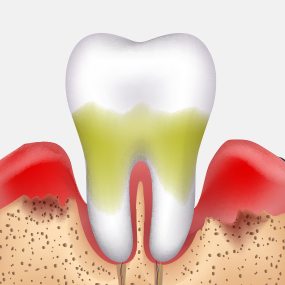

치아에 남아있는 음식물 찌꺼기나 치태, 세균 덩어리들이 타액 성분과 결합하면 치아와 잇몸 사이에 돌처럼 굳어지는 치석이 생기며, 치석은 잇몸질환, 충치를 유발하는 원인으로 제거해야 합니다.

붓고 피나는 잇몸을 건강하게 잇몸치료로 회복하세요!

건강한 치아는 건강한 잇몸이 있기에 존재합니다. 성인의 절반 이상이 잇몸 질환을 모르고 방치하고 있습니다. 잇몸질환, 꾸준한 관리를 통해 개선해드리겠습니다.

잇몸 질환 치료에는 비수술적 치료와 수술적 치료 방법이 있습니다.

건강한 잇몸

치주낭 길이 3mm 이하

스케일링 치료

치은염

치주낭 길이 3~5mm 이하

치근활택술 치료

초기 치주염

치주낭 길이 5~7mm 이하

치주소파술 치료

중기 치주염

치주낭 길이 7mm 이상

치주 수술